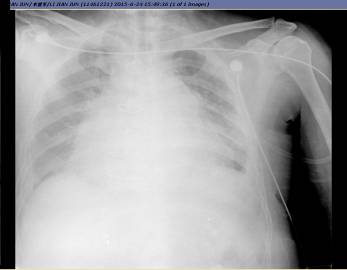

2.超滤前后胸片变化

超滤前

超滤后2日